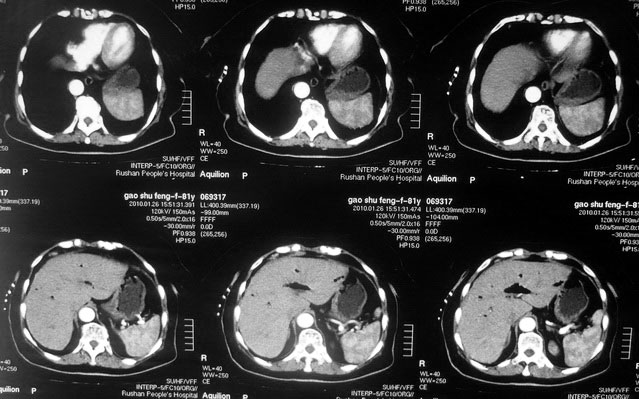

女,80岁既往有胆系手术史。近2月出现食欲不振,近20天出现畏寒发热,体重约下降10kg,体温一般在38℃左右。血常规wbc正常,中性比例88%,cea 10.3,afp、ca199均正常。做过一次肝穿,抽出约3ml仿佛脓性液体。这是她的增强ct扫描,请大家帮帮忙。另外想问问肝脓肿和胆管细胞癌的ct表现有什么区别。谢谢了。

【湘江一滴】化脓性胆囊炎及胆管炎,肝内胆管积气、积液、扩张;胆囊壁增厚、强化;胆周积液。未见肝内占位征象。

【shuiyuan】化脓性胆囊炎及胆管炎,肝内胆管积气、积液、扩张;胆囊壁增厚、强化;胆周积液.

肝脓肿动脉期呈明显环形强化或蜂窝状强化,胆管细胞癌动脉期强化不明显,且伴肝内胆管扩张。

【zenxisengming 】肝内胆管扩张积气,胆囊比环形增厚,胆囊周围渗出,未见占位性病变,应该是胆道化脓性感染

【sunbin】肝内见多个气体密度影伴气液面,胆囊壁增厚,胆囊周围低密度环绕,未见强化,支持化脓性胆管炎、胆囊炎。

最近复查ct,做了第二次穿刺抽脓,顺便做了涂片病理活检,结果找到恶性肿瘤细胞,诊断肝癌合并肝脓肿。看来大家都走眼了啊。